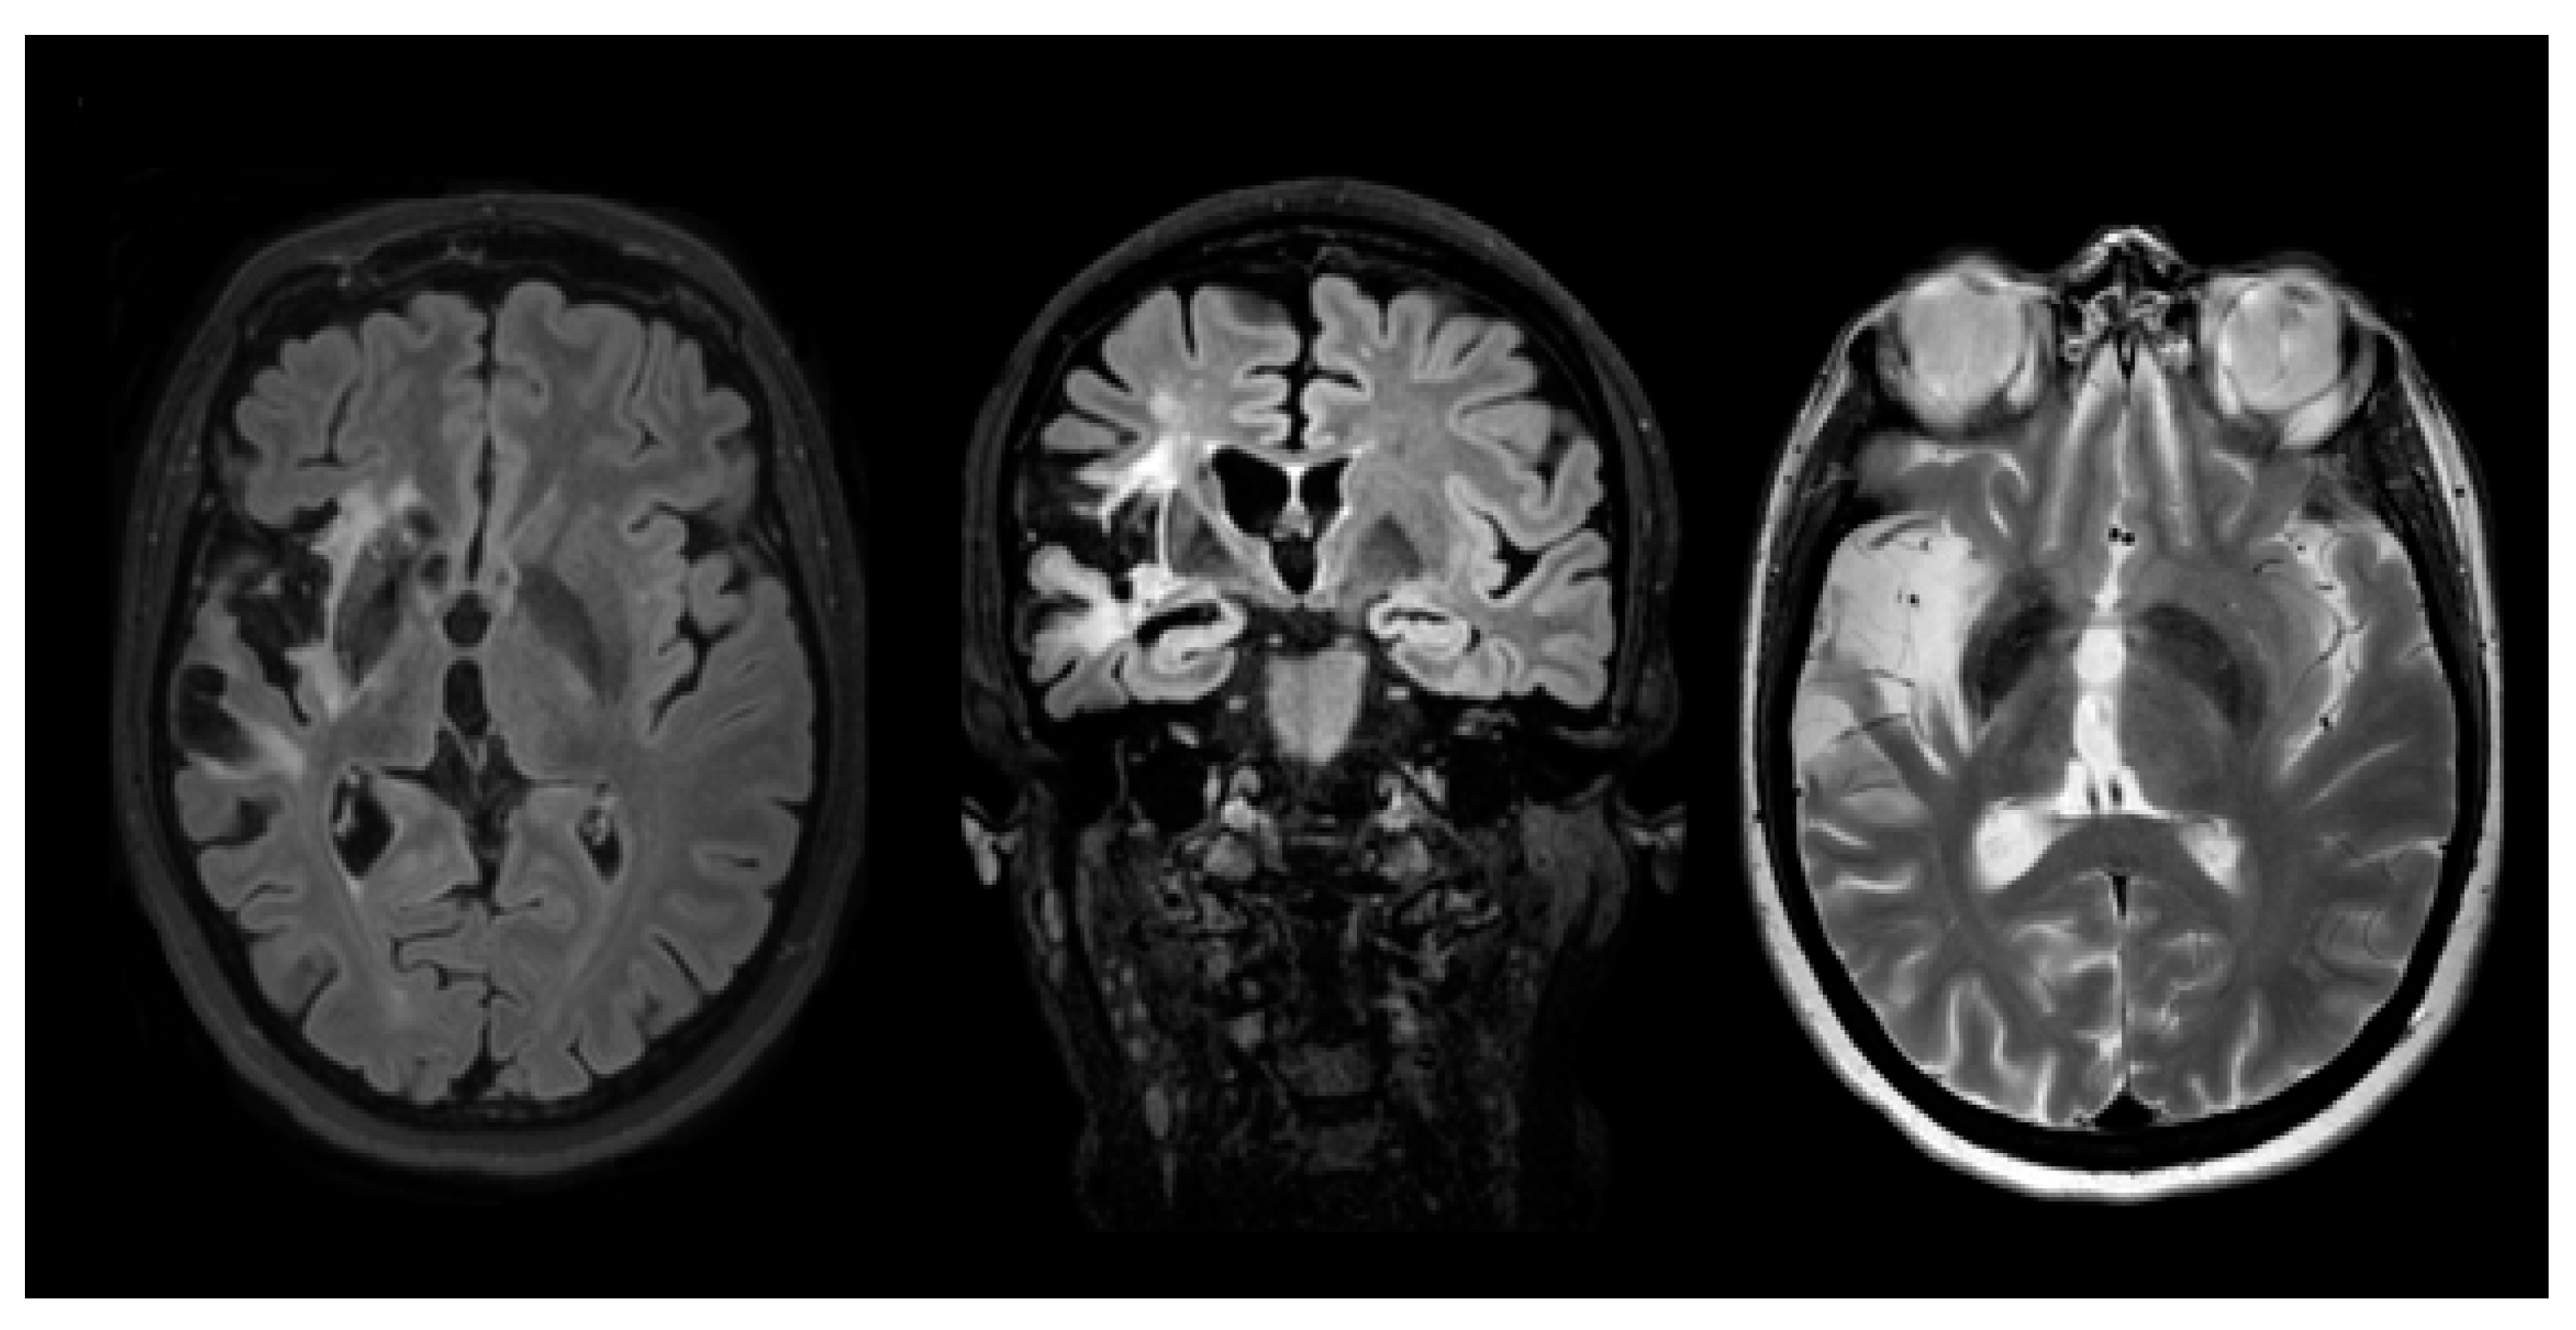

2. Case Presentation